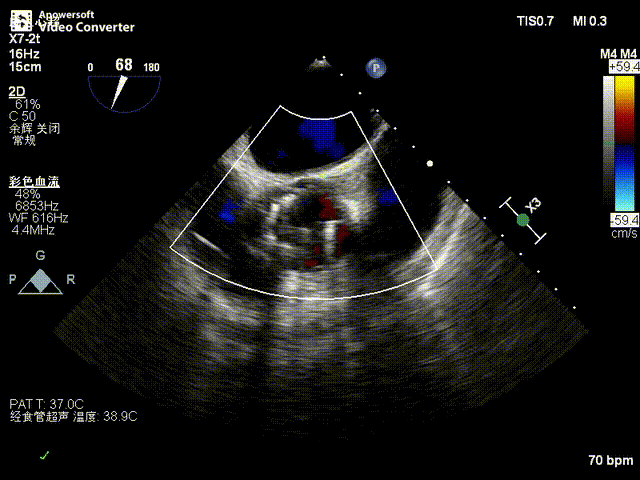

患者全麻后,于左侧心尖3-4cm处进行微创手术切口。在DSA及超声引导下,输送Ken-Valve瓣膜系统进入左心室,边调弯边推送,使得瓣膜在术中始终保持较好的同轴性,从送入输送器到瓣膜释放不足十分钟。术后即刻患者反流消失,于外科杂交手术室拔除气管插管,次日即由ICU转入普通病房。

术后超声影像图